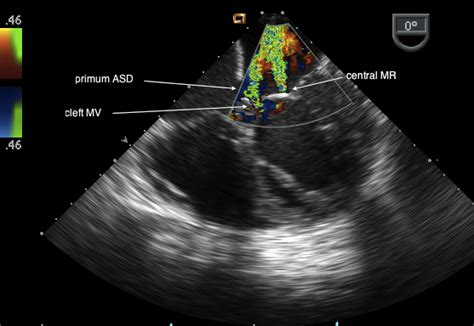

Coronary Sinus Asd Repair / Atrial septal defect / It is present in all mammals, including humans.. Coronary sinus atrial septal defect. This is very rare variety. Coronary sinus atrial septal defect is a rare congenital cardiac anomaly in adults. Therefore, surgical asd repair is not recommended in this setting. Thickened mitral leaflet at margin of cleft.

This type is classified as partially unroofed coronary sinus without lsvc. Coronary sinus asd occurs when there is a defect in the wall between the coronary sinus and the left atrium. Atrial septal defect can be small, moderate and large in size. After the repair, your child's doctor may want your child to take antibiotics. The mitral valve cleft is repaired felted mattress sutures are placed beneath the coronary sinus for use in the asd repair. Thickened mitral leaflet at margin of cleft. Ignoring this cardiac defect, especially of big sizes, can give rise to serious complications like pulmonary hypertension, endocarditis and heart failure. Atrial septal defect (asd) is one of the most common congenital heart defects with a prevalence of isolated defect ranging from 0.5 to 2.5 cases per 1 in most patients with isolated asd and without pulmonary hypertension (ph), there is a left to right shunt.

Coronary sinus type of defect of asd: An asd occurs when part of the atrial septum does not form properly. This defect is located within the wall of the coronary sinus, where it passes behind the left atrium. Ostium primum asds and sinus venosus asds do not close spontaneously. Asds which can only be closed by surgical means include sinus venosus, coronary sinus and primum septal defects. These stitches are superficial and on the left atrial surface. Significant coronary artery disease was found in 2 of 27 patients undergoing coronary angiography. This heart defect can over time cause lung problems if not repaired.